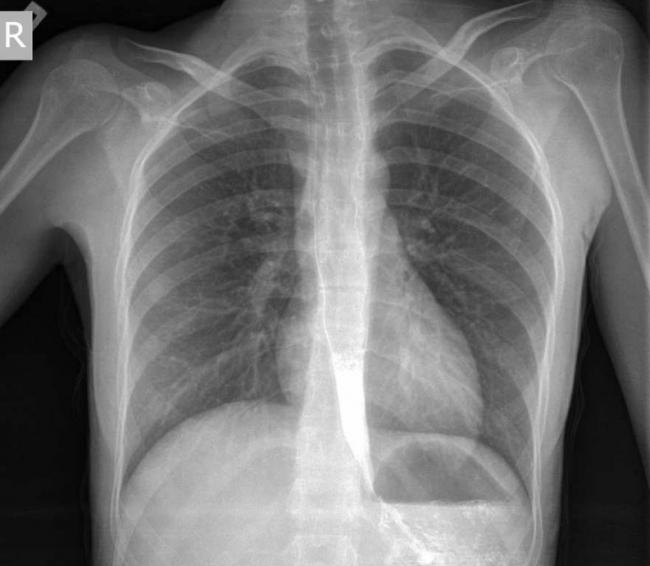

- Рентгенография грудной клетки. Обследование начинается именно с данного исследования. В случае выявления на рентгенограмме тени расширенного пищевода с жидкостным уровнем назначается рентгенография пищевода, предполагающая предварительный прием бариевой взвеси. Если имеет место ахалазия кардии, то становится заметным сужение конечного отдела пищевода, а также расширение участка, располагающегося выше.

- рентген грудного отдела;